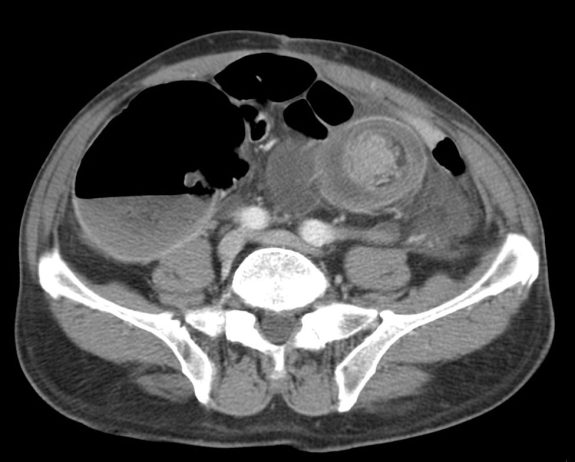

La obstrucción intestinal es una condición médica común que se presenta frecuentemente en el servicio de urgencias. Esta afección puede involucrar tanto el intestino delgado como el colon, siendo responsable…